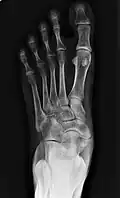

Type 2 -